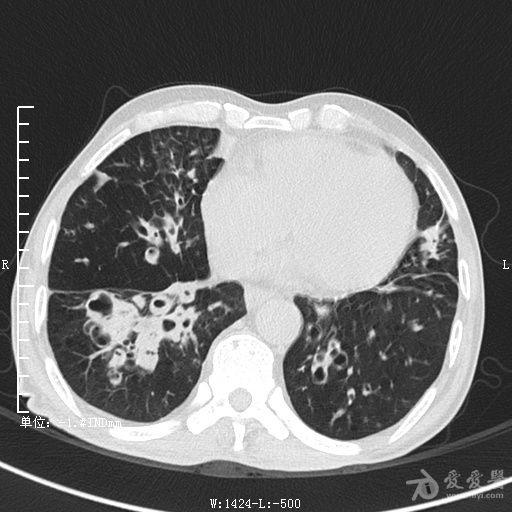

典型支气管扩张及肺水肿CT片

典型支气管扩张肺水肿